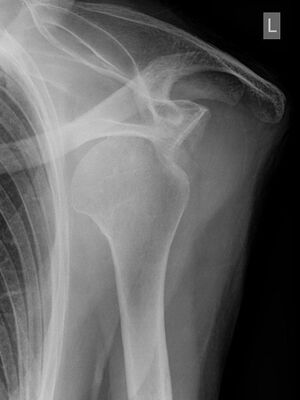

Röntgenbild einer ausgerenkten Schulter - Hellerhoff commons.wikimedia.org, CC BY-SA 3.0

Eine Schulterverrenkung wird häufig durch einen Sturz auf den ausgestreckten Arm oder durch einen starken Zug am Arm ausgelöst. Diese Verletzung treten häufig beim Skifahren, Eishockey, Handball oder Turnen auf.

Bei einer „ausgekugelten“ Schulter steht der Oberarm seitlich vom Körper ab, die normalen Umrisse des Schultergelenks sind verändert, der ausgerenkte Oberarmkopf und die Gelenkpfanne sind tastbar.